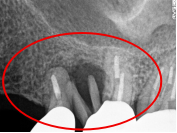

Before

※赤丸は、歯根が破折していたため抜歯しました

※黄色丸は、2006年10月に埋入したインプラント